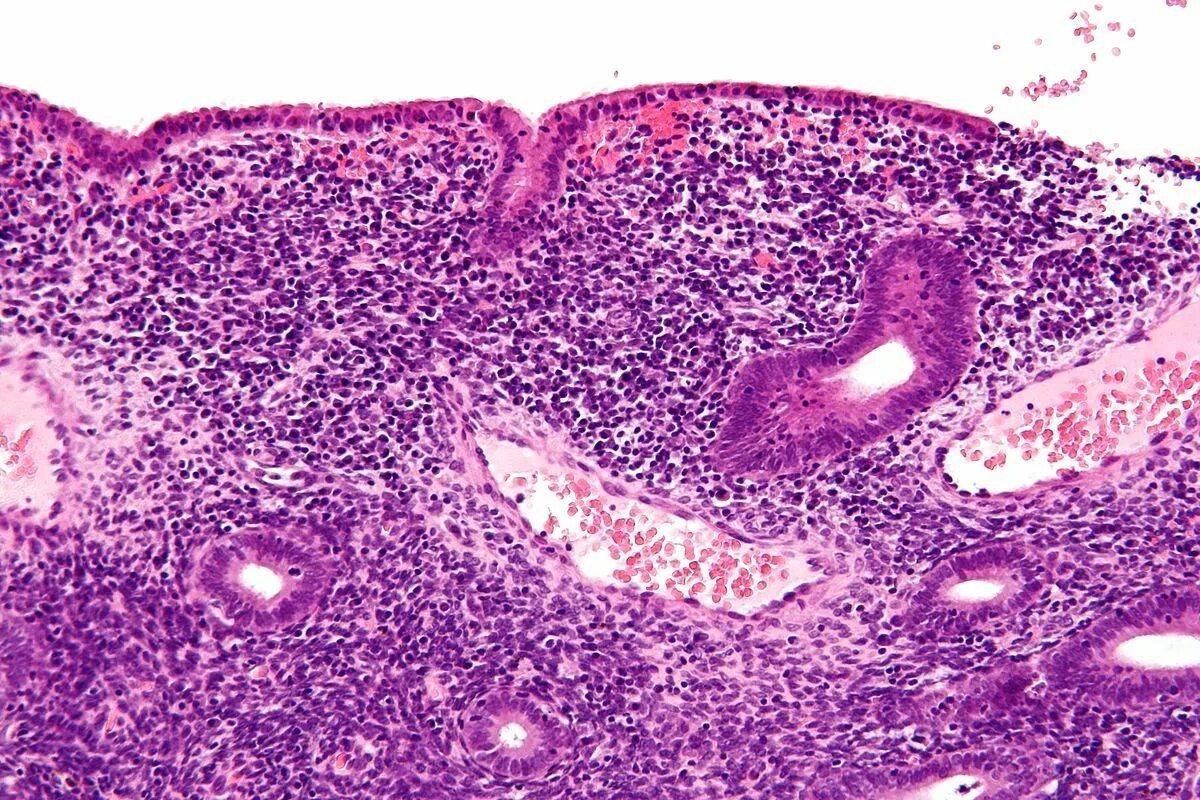

Эндометрит гистология